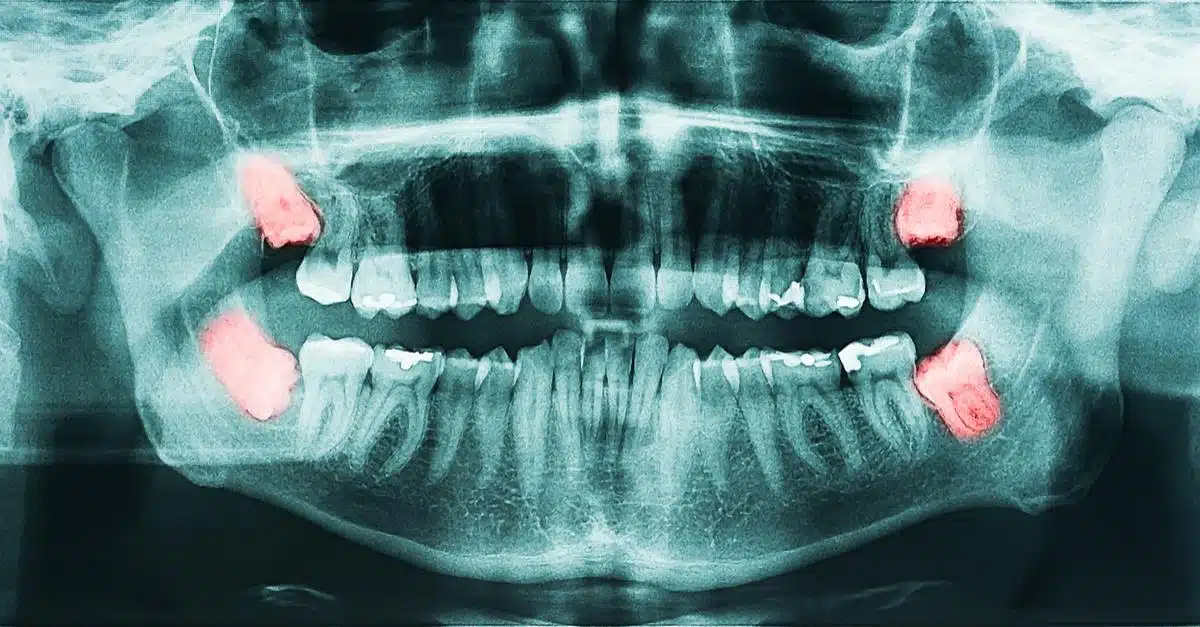

Radiografía de una boca con muelas del juicio en rojo

Recomendamos realizar la exodoncia de los terceros molares o ‘muelas del juicio’ cuando aparecen mal alineados en los maxilares y suponen un riesgo hacia el bienestar de los molares sanos que tienen al lado.

En muchas ocasiones, las muelas del juicio aparecen horizontales respecto al plano correcto de erupción e impactados en los segundos molares, aumentado el riesgo de que estos puedan padecer caries en zonas difícilmente restaurables y también tengamos que extraer.

Las muelas del juicio no siempre hay que extraerlas. Cuando estas son visibles en una radiografía rutinaria o aparecen en boca, sólo debemos controlar su evolución y, si no dan problemas y no suponen un riesgo hacia las estructuras vecinas, las mantendremos en boca sin ningún problema.

Quien mejor nos puede asesorar acerca de qué debemos hacer con las muelas del juicio es nuestro odontólogo de confianza. Este nos hará controles radiográficos periódicos para ver su evolución y determinar si derivar, o no, a nuestro cirujano para su extracción.